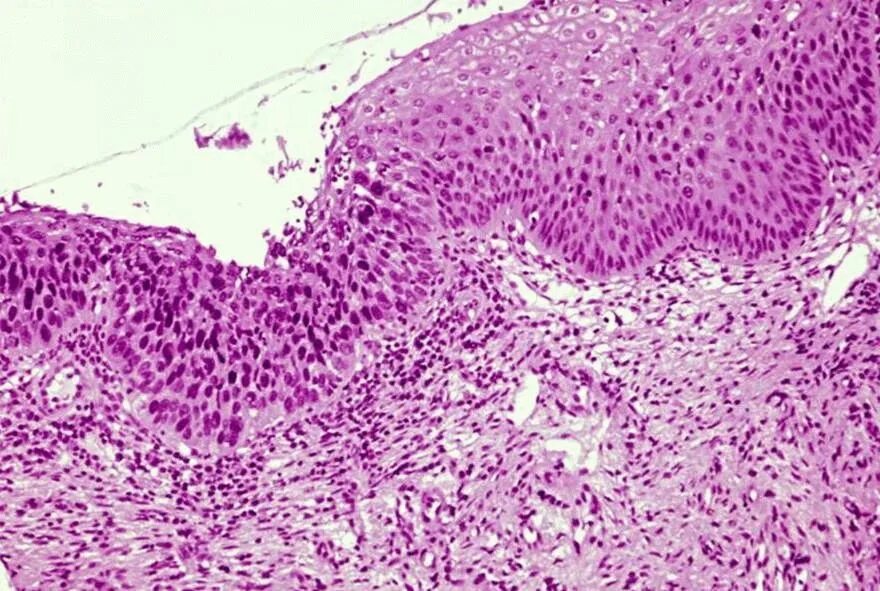

Cin 0